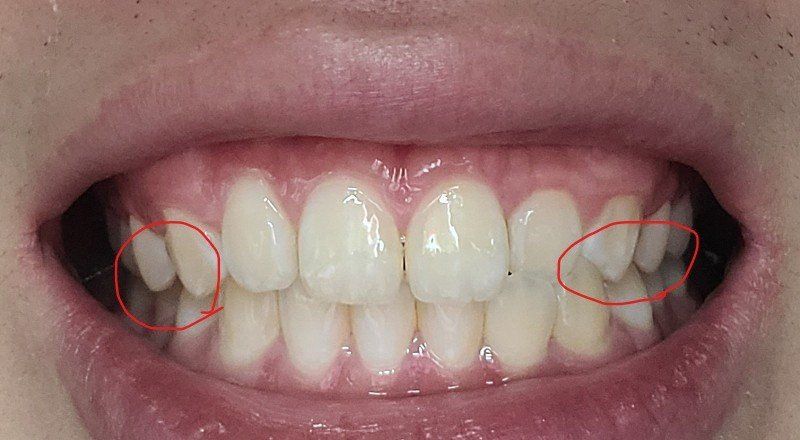

송곳니랑 그부근 어금니가 좀 더 틀어져서 깊게?물려요 턱이 비대칭이있긴한데 이정도비대칭은 사람마다 있다고들 하는데

-한쪽 송곳니은 살짝 떠있고 반대쪽은 잘물려요

왜 그런건지 모르겠어요 중심선이 안 맞아서 그런 건가요?

-만약 교정을하게 된다면 전체교정을 해야하나요?

-제경우에 클리피씨하는거랑 인비절라인으로 하는거랑 차이가 있을까요?

- 사진상으로 보면 크게 교정이 필요하실꺼 같진 않습니다. 만약 교정을 하게 되신다면 교정분석을 해봐야 전체 교정을 할지 부분교정을 할지 판단할수 있습니다.

2.제경우에 클리피씨하는거랑 인비절라인으로 하는거랑 차이가 있을까요?

-클리피씨와 인비절라인은 단순 비교할게 아니며, 케이스에 따라서 선택해야되야됩니다. 크게 치열에 문제가 없으셔서 인비절라인으로 하셔도 효과를 볼수 있을것같습니다.